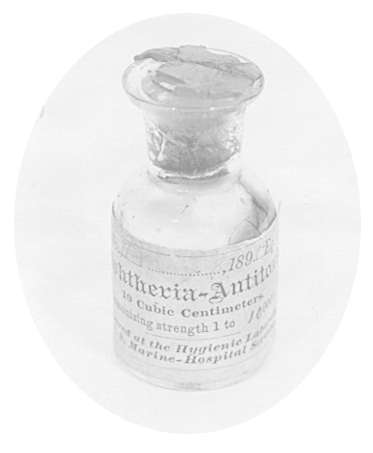

1890年12月4日

日本医生Shibasaburo Kitasato和德国生理学家Emil Adolf von Behring发现白喉杆菌的免疫方法。他们让兔子对破伤风杆菌免疫,获得血液,将血清注射到小鼠体内,再将小鼠与破伤风梭菌接触,发现小鼠可以表现为对常规毒素作用的免疫力。他们的研究论文提出了术语"抗毒素"(antitoxin)。一周之后,Behring发表了动物对白喉免疫的研究的论文,并因此获得了1901年的诺贝尔奖。

第一个诺贝尔医学奖授予了Emil Adolf von Behring,他发明了治疗白喉的"血清疗法",使白喉的死亡率得到了极大的下降。最终,白喉在世界范围内绝迹。